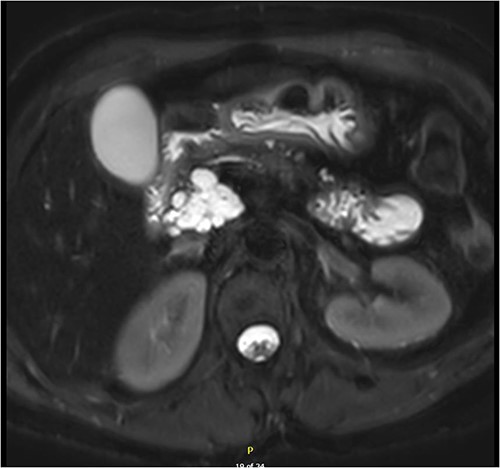

Interval MRI after 1 year showed an increased size of 8 cm with associated main pancreatic duct dilation up to 8 mm, which was not previously present (Fig. 2). Repeat EUS and biopsy demonstrated atypical cytology. The presence of atypical cytology and progressive duct dilation suggested the possibility of a malignant process and surgical resection was recommended.

Increased diameter of lesion and dilation of main pancreatic duct on interval MRI.